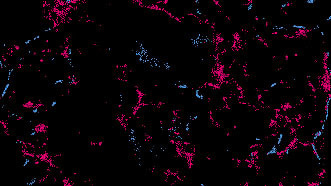

But their combined role—a toggle between lipid domains dictating receptor activity—was unexplored. Using super-resolution imaging, we saw GABAAR physically shift from saturated to unsaturated lipids upon activation (Figure 1). Crucially, this movement was triggered not just by anesthetics, but by GABA itself, suggesting positional regulation is intrinsic to neurotransmission.

Positional activation of GABAAR by neurotransmitter.